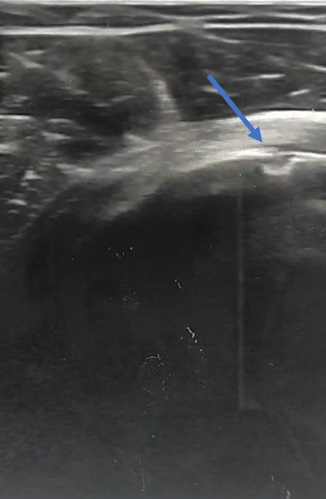

• Se realizó una ecografía, en la que se apreció una solución de continuidad en la cortical del húmero que hizo pensar en una avulsión del tendón del músculo subescapular.

• Juicio clínico: avulsión del tendón del músculo subescapular del hombro derecho.